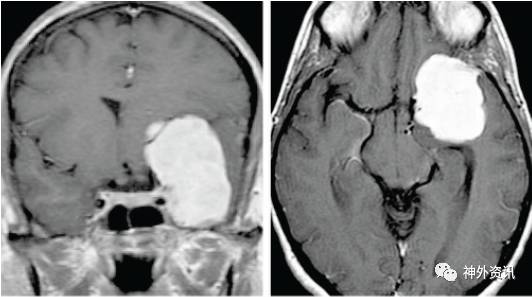

图2:一例巨大的内侧型蝶骨嵴脑膜瘤(上图),经改良眶颧入路完整切除(中图)。该例肿瘤向上显著生长,因此需要通过切除眶顶骨质来获得从下至上的手术视野。同样地,另一例三脑室型颅咽管瘤(下图)也通过相同的入路经终板切除。